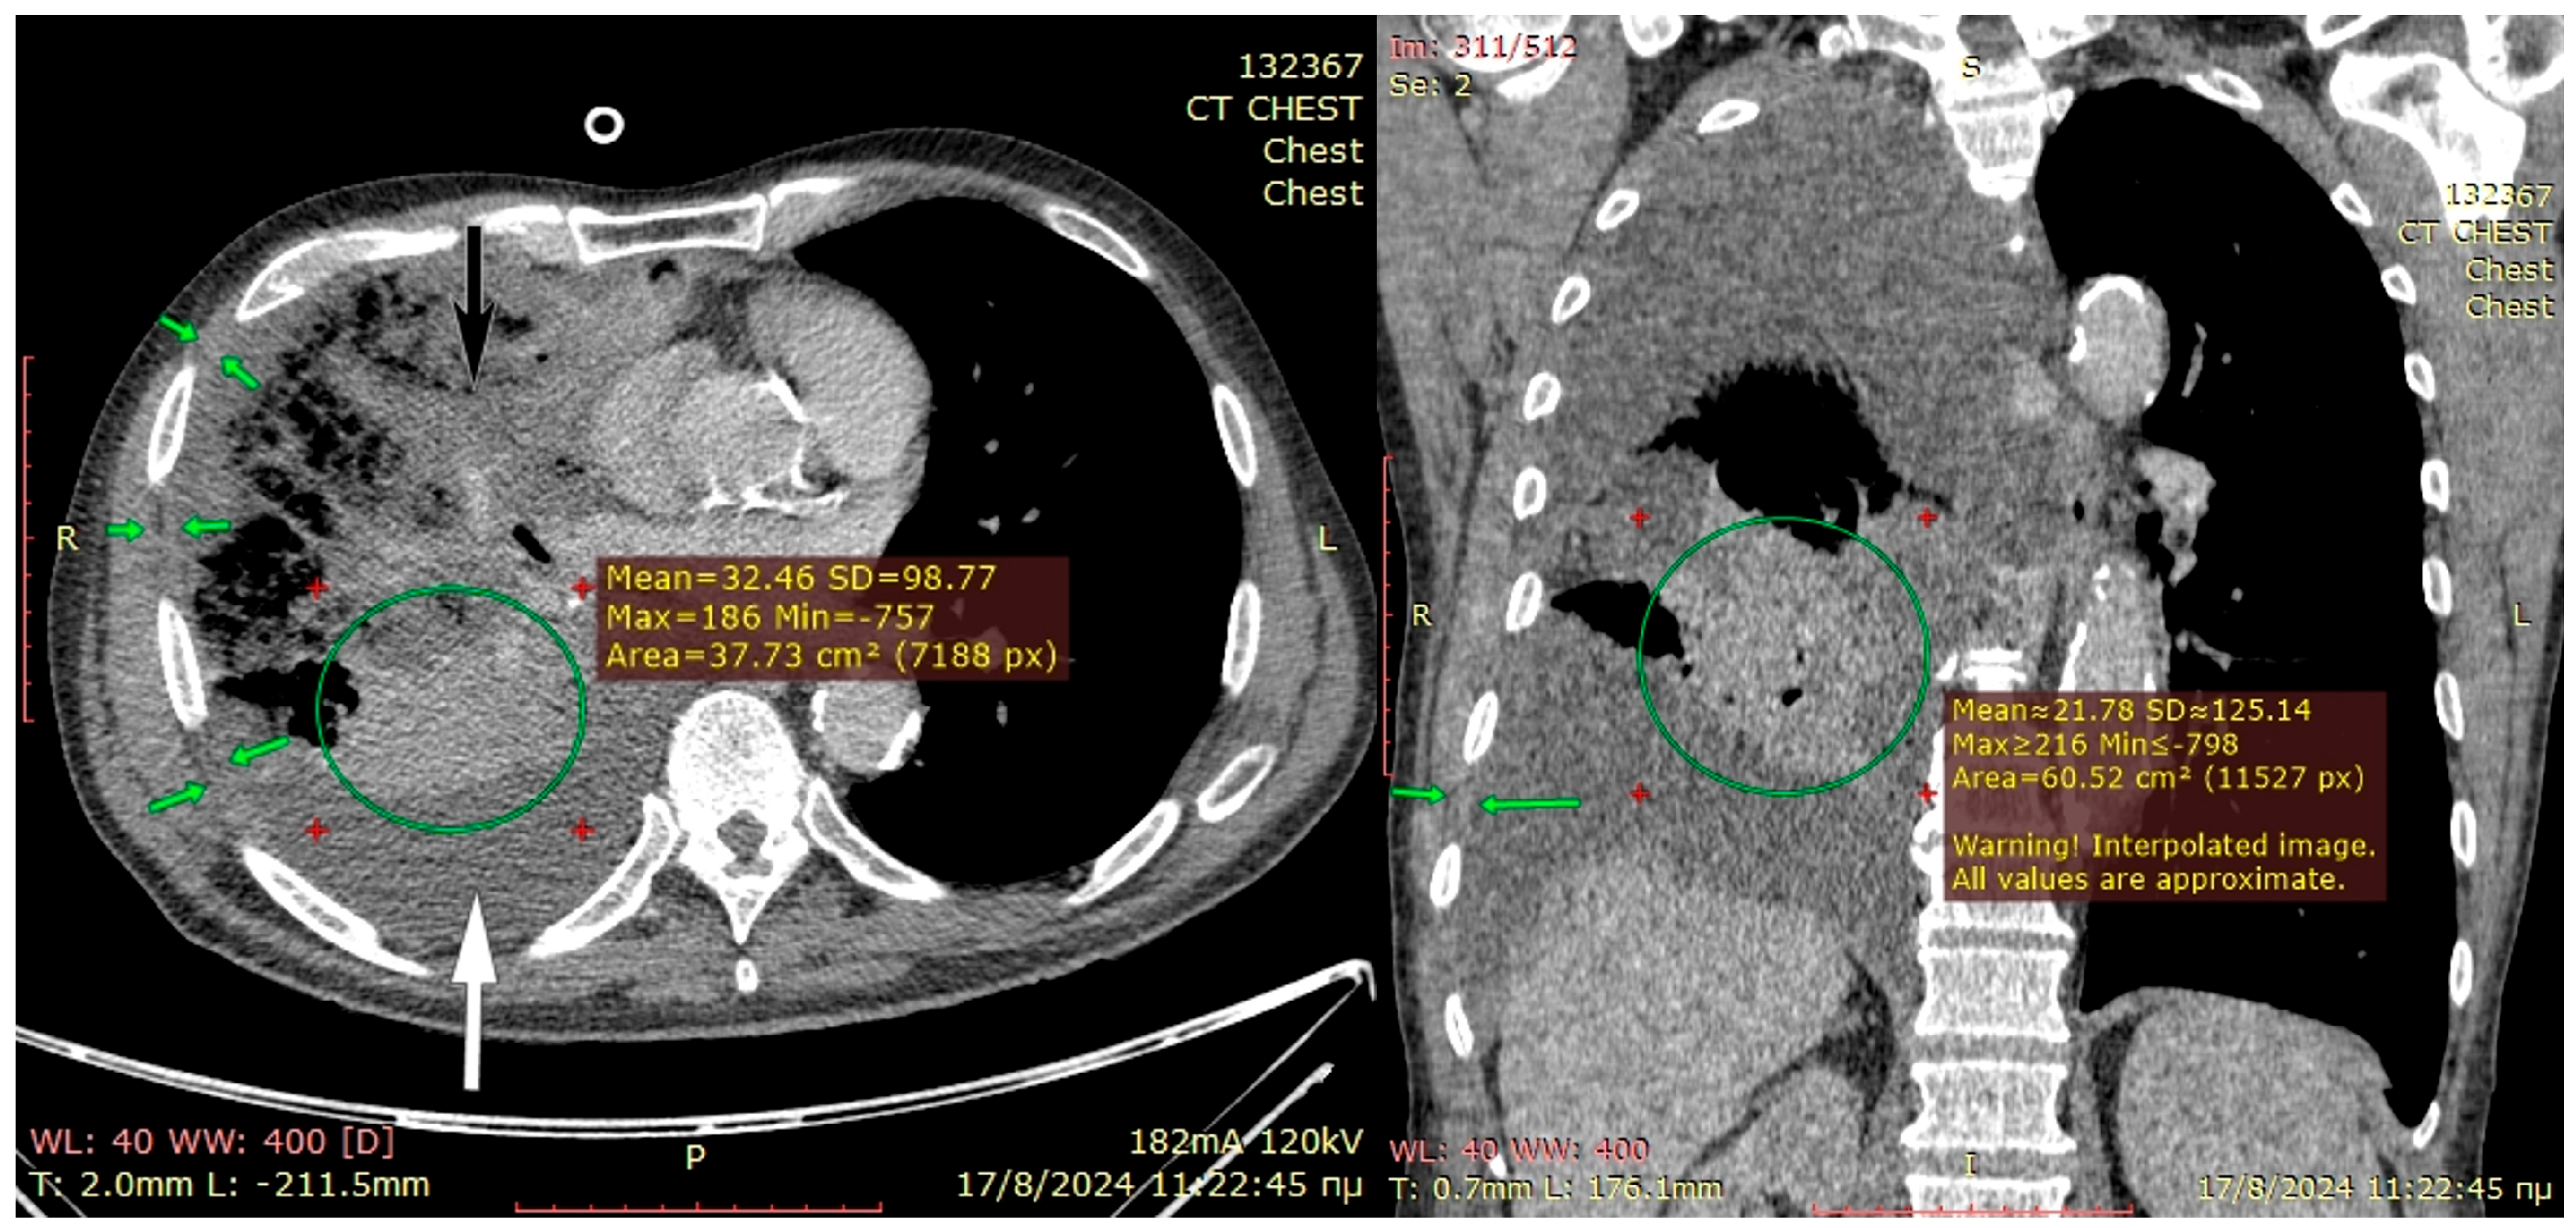

A 75-year-old male cachectic smoker of low socio-economic status underwent improperly treated antibiotic-resistant right-sided pneumonia with parapneumonic effusion due to Gram-positive cocci in pleural fluid. He underwent several unsuccessful pleural drainage procedures, including small-bore Seldinger type tubes and twice closed tube thoracostomy, failing to re-expand the right trapped lung and control the pleural infection.

The preoperative CT scan is shown in Figure 3. The patient became septic and developed middle-lobe necrosis, for which he underwent an acute open lobectomy combined with an unsuccessful decortication of the remaining two lobes due to emphysematous frail parenchyma and post-operatively had limited recovery from sepsis. He was scheduled two weeks later for window thoracostomy and vac-therapy. At re-thoracotomy, the thickened parietal pleura was easily mobilized from the chest wall; therefore, the intercostal muscles were carefully dissected off the ribs and, along with the thick pleura, were placed deep in the pleural cavity and sutured at the right hemidiaphragm and lower lobe visceral pleura, using prolene 3-0 sutures. Two chest drains were inserted, and a vacuum device was applied in the subcutaneous space, rather than a drain, because the skin and subcutaneous layers were inflamed from the thoracotomy for middle-lobectomy that had been performed 4 weeks earlier. The patient recovered from pleural sepsis with vacuum therapy discontinued after 4 weeks with good wound healing. He remained afebrile and hemodynamically stable without any supplemental oxygen, and free from a demanding thoracostomy window that would require months-long attendance by specialist nurses.

Figure 3. Preoperative planning CT-scan for Case 2 where the severely infiltrated middle lobe (black arrow) mandates salvage lobectomy to avoid gangrenous conversion and sepsis. The lower right lobe (green circle) is grossly atelectatic, but assessing its viability and attempting decortication is only possible through thoracotomy. The green arrows in both pictures show a moderate chest wall thickness. The decision for Sawamura can only be undertaken intraoperatively. An open thoracostomy window could also be offered to this patient if only the community can offer daily dressing changes.